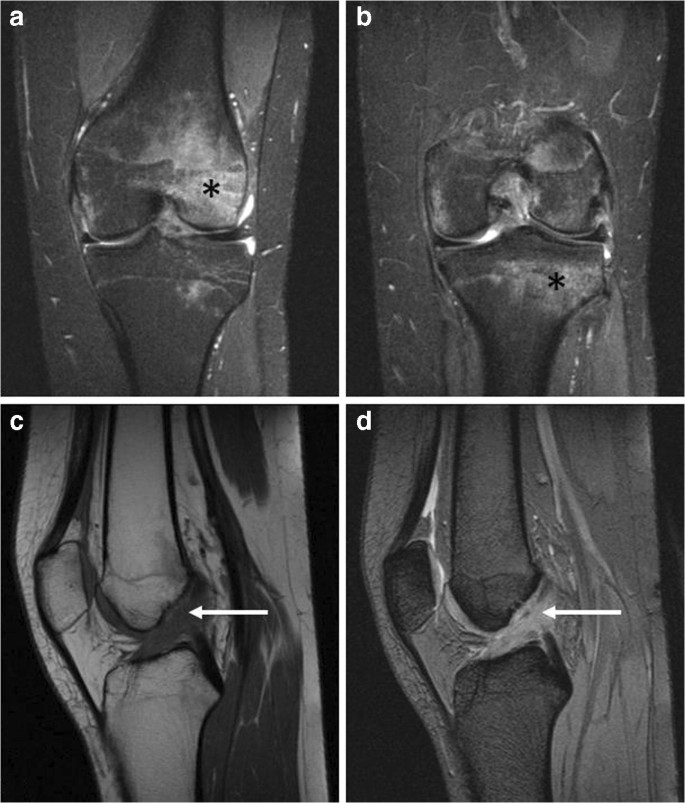

Diz dışı bölgelerde Kemik Kanalı Hipervaskülarizasyonu teşhisi, genellikle ileri görüntüleme teknikleriyle konulur. MRI, bu sendromun tespitinde altın standart olarak kabul edilir. Kemik iliğindeki ödem ve hipervaskülarizasyon, MRI görüntülerinde belirgin bir şekilde ortaya çıkar. Bunun yanı sıra, röntgen ve bilgisayarlı tomografi (BT) gibi yöntemler de destekleyici olarak kullanılabilir.

Kemik Kanalı Hipervaskülarizasyonu, kemik iliğinde artan kan akışı ve buna bağlı olarak gelişen ödemle tanımlanan bir durumdur. Bu sendrom, genellikle travma, stres kırıkları veya altta yatan başka bir patolojik durum nedeniyle ortaya çıkabilir. Kemik iliğindeki bu anormal durum, manyetik rezonans görüntüleme (MRI) gibi ileri görüntüleme teknikleriyle kolayca tespit edilebilir. Ancak, diz dışı bölgelerde görüldüğünde, teşhis süreci daha karmaşık hale gelebilir. Bu durum, hem hasta hem de hekim için zorlayıcı bir tablo oluşturabilir, çünkü belirtiler diğer hastalıklarla kolayca karışabilir.